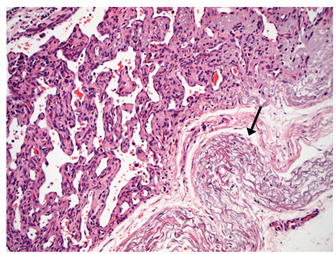

Moderate to marked cellular pleomorphism and nuclear atypia were seen in all cases. Mitoses per 10HPF (2.73 mm2), varied from 3 to 34 per HPF, with case 4 displaying the highest number of mitoses and the only case with metastatic spread (Fig. 4). Solar elastosis was seen in five cases (Fig. 5).

In the two horses diagnosed with conjunctival angiosarcoma, the histopathological findings reflected malignant conjunctival neoplasms that were poorly differentiated with regards to lineage. Both of these neoplasms had a solid epithelioid growth pattern and an absence of vascular channel formation, but vascular lineage was suspected given the location and H&E morphology of the tumour, accompanying perivascular lymphonodular aggregates and absence of overlying surface epithelial pathology with regards to dysplastic or neoplastic changes to indicate carcinoma (Fig. 6). IHC was performed in these two cases in an attempt to rule out the differential diagnosis of carcinoma and confirm vascular lineage as a requirement for further tumour identification (Fig. 7).

Fig. 5. H&E photomicrograph (100× magnification) of case 2 bulbar conjunctival haemangiosarcoma from a horse characterised by irregularly branching, blood-filled vascular channels. There is evidence of solar elastosis in the conjunctival stroma (arrow).

In Figure 8, a conjunctival haemangiosarcoma displays the more “classical” gross appearance of haemangiosarcoma; an exophytic mass with red appearance to both the cut surface and on histopathology. Blood-filled channels lined with neoplastic cells provide the tumour with a red appearance. Although clinically appearing as a discrete mass, the invasive nature of this tumour type can be seen with neoplastic cells infiltrating the cornea outside the mass. Contrast this to Figure (6), a poorly differentiated, solid angiosarcoma. Whilst still marginally exophytic, the gross appearance was cream/pale coloured, and histopathology revealed a lack of blood vessels. The tumour was solid in appearance with poorly differentiated cells making classification difficult. This highlights the importance of haemangiosarcoma as a differential for conjunctival masses in a horse, even if their appearance is not grossly red.